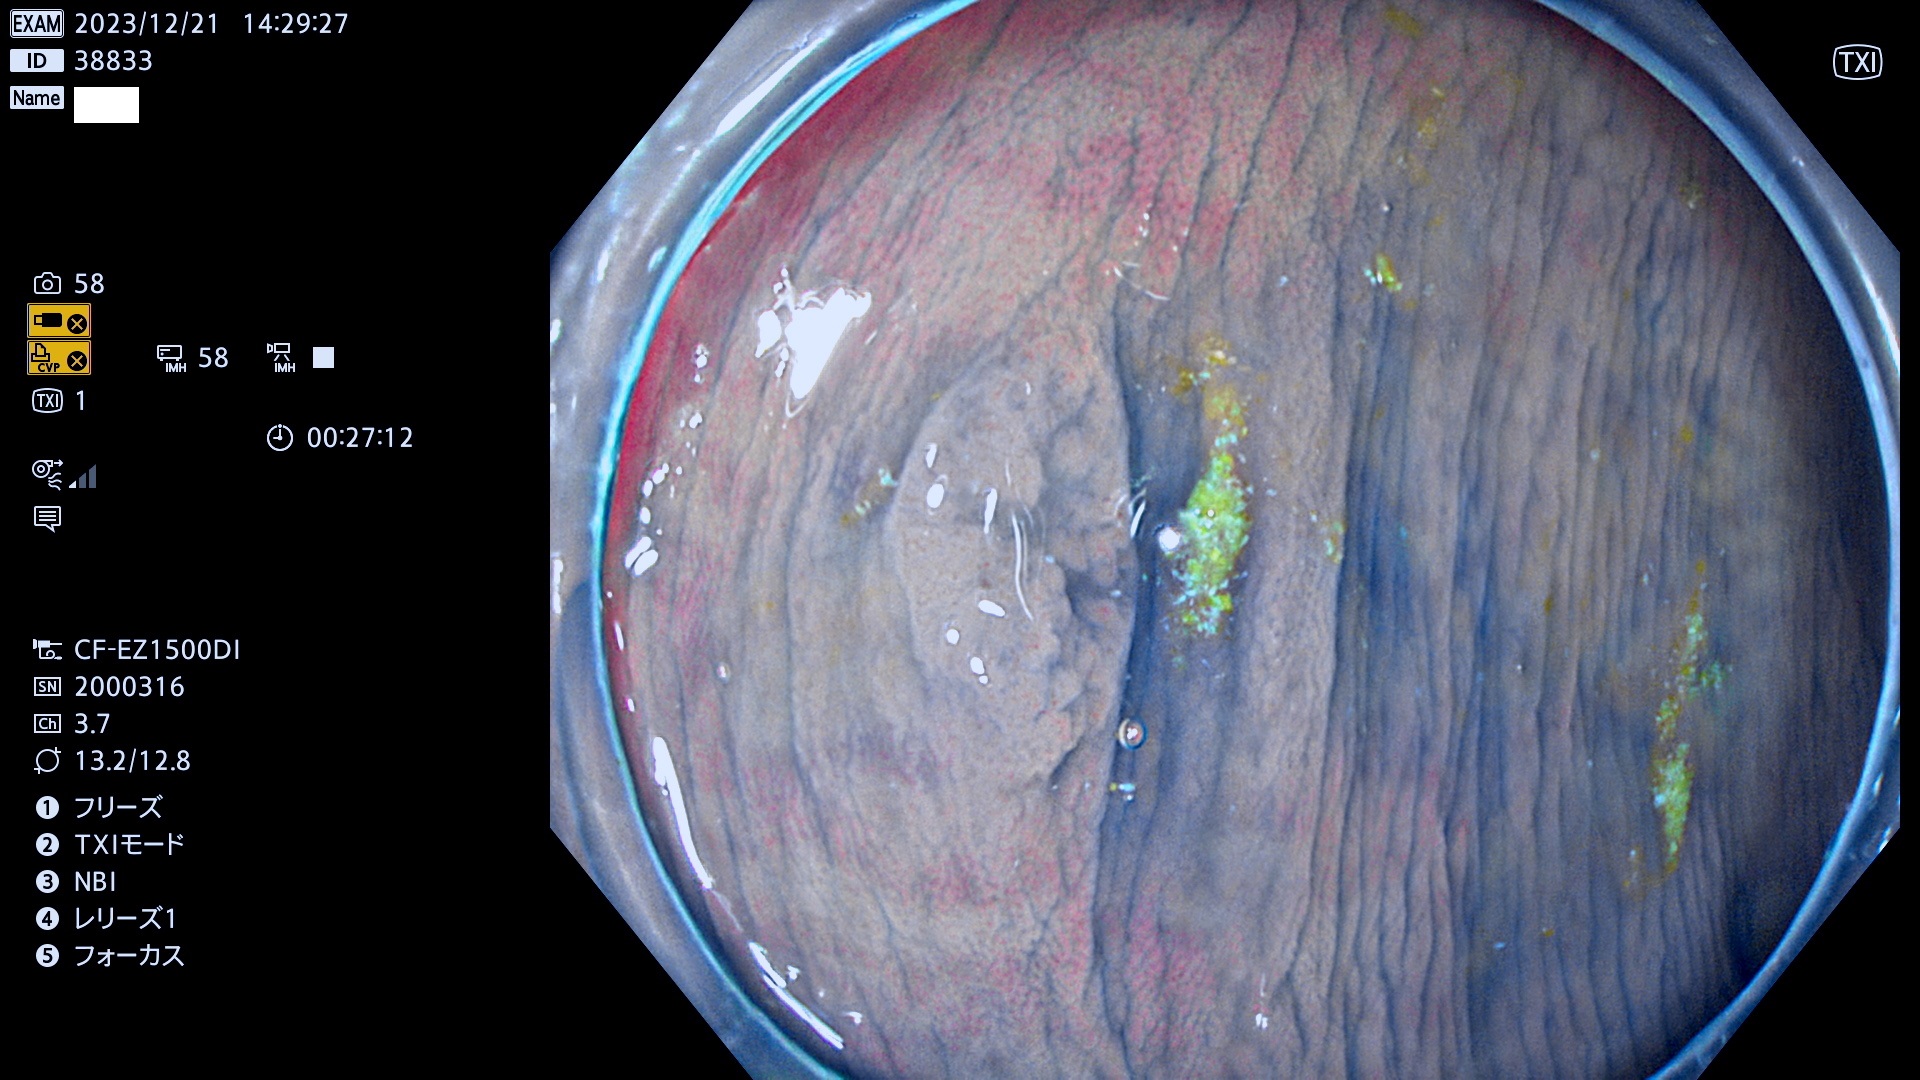

表面型腺腫(Flat Adenoma)の中で、完全に平坦な物をUb、陥凹している物をUcと呼びます。平坦隆起型(Ua)よりも、発見が難しく危険な病変です。

当院で見つかった、炎症(ビラン)と極めて紛らわしい腺腫の例